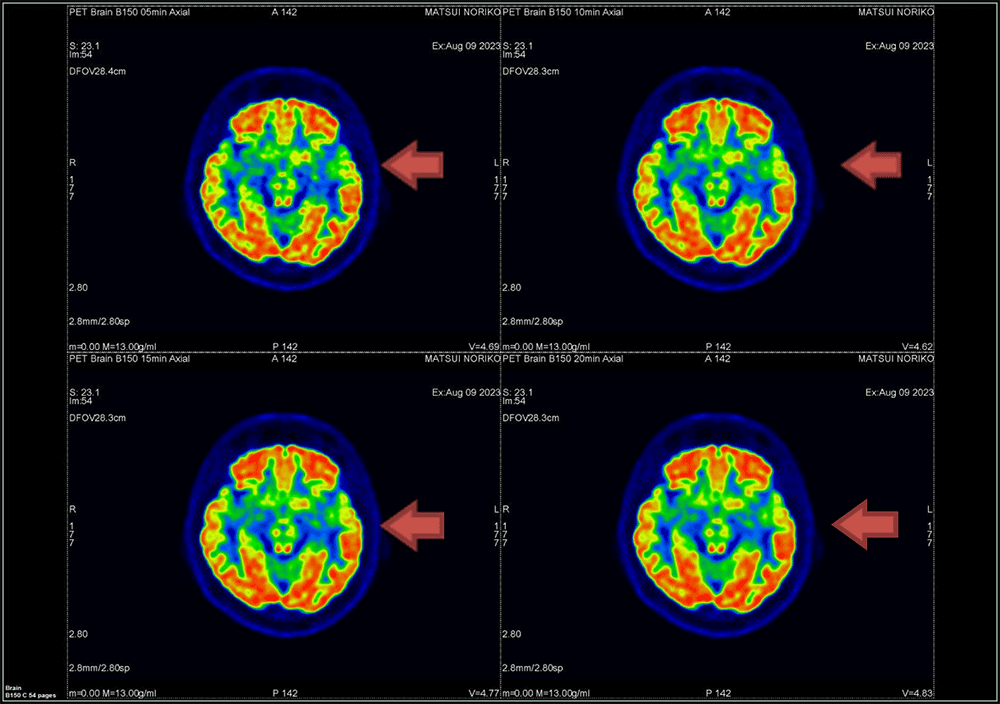

② Q.Clear法

β値150のQ.Clear画像をFig.6に示す。分解能の視覚評価では、マトリック数256以上では差を認めませんでした。

Fig.6 描出能の視覚評価 Q.Clear法(β150)